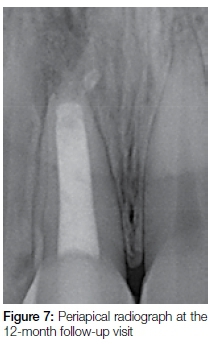

At a follow-up consultation and evaluation four weeks later, it was observed that there was no visible swelling, there were no clinical symptoms on percussion and palpation of the tooth, and no mobility could be demonstrated. The patient was re-scheduled for an eight-month follow-up at which time notable bone healing with a reduction in diameter of the periapical lesion was seen (Figure 6). On a 12-month post-operative follow-up visit, examination of a periapical radiograph confirmed clear signs of bone healing and reduction of the large apical radiolucency (Figure 7).